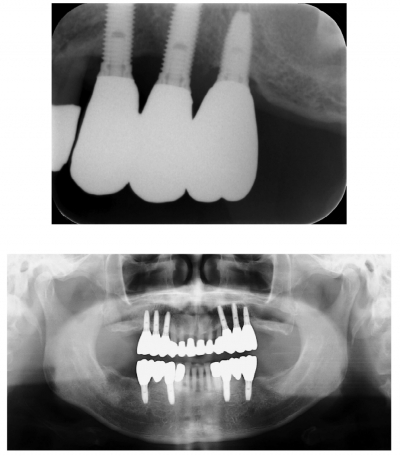

53歳の男性。上顎左側臼歯部の腫脹と出血を主訴として来院した。6年前に同部の加療を受け、メインテナンス期間中は良好に経過していたが、2か月前からブラッシング時の出血を自覚しているという。プロービング前後の口腔内写真とエックス線写真を別に示す。

診断はどれか。1つ選べ。

d. インプラント周囲炎

e. インプラント周囲粘膜炎